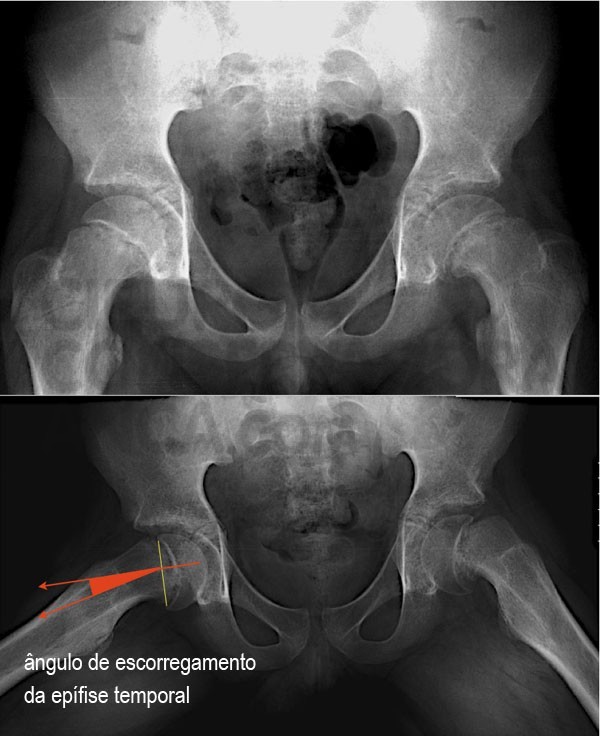

O diagnóstico é feito com base nas queixas da criança e implica um grau de suspeição clínica importante. A radiografia anteroposterior pode ser normal por isso é muito importante a incidência de perfil onde o escorregamento posterior normalmente é bastante evidente. (fig 1)

Figura 1: Em cima radiografia antero-posterior de uma criança com 12 anos e uma epifisiolise bilateral e a respectiva metedologia de medição do ângulo de escorregamento da epífise.